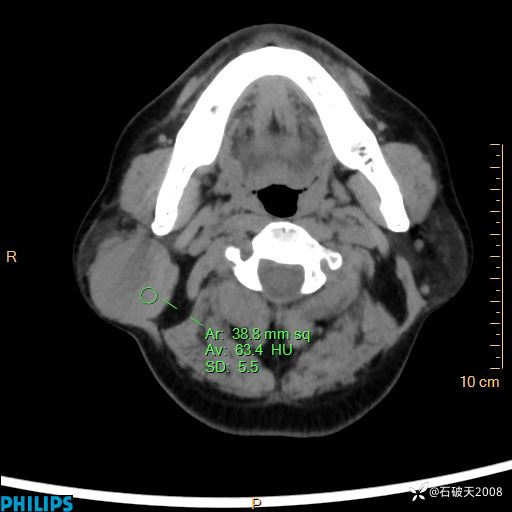

病例分享:颈部占位,一周后公布病理

男 57岁 主 诉:发现右侧颌下肿物1月余。

现病史:1月余前家属发现右侧颌下肿物。局部皮肤无红肿、热痛,无吞咽困难,无异物感,无恶心、呕吐,无头痛、头晕,无胸闷、胸痛,无发热、咳嗽、咳痰及呼吸困难。于我院行体表肿块彩超检查(2024.03.15我院)示:右侧耳下皮下软组织内低回声,未治疗。今为进一步治疗门诊以“腮腺肿瘤”为诊断收住我科,发病来患者神志清,精神可,饮食、睡眠及大小便正常,体重无明显下降。

静脉期